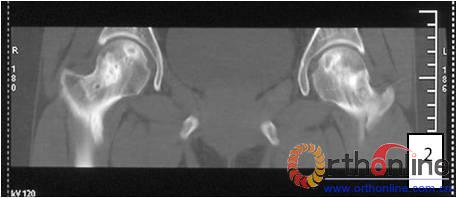

图3-1 女,31岁,SARS患者骨坏死,(1)MRI示双侧股骨头坏死,右Ⅱb(B型),左Ⅱc(C1型);(2)打压植骨术(未加BMP2)后坏死修复不完全,仍遗留股骨头软骨下病灶未完全修复, 5年随访关节功能优(Harris评分96分)

图3-2 女,30岁,SARS患者骨坏死,(1)术前MRI示双侧骨坏死;右Ⅱc期C3型,左Ⅱb期B型,打压植骨术(加BMP2),(2)5年后CT显示病灶修复好,关节功能优